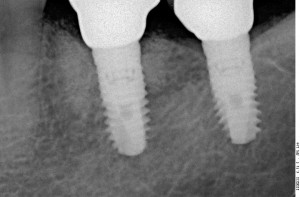

Прицельный радиовизиографический снимок можно сделать в любой из наших клиник. В отличие от обычных прицельных рентгенограмм зубов, доза лучевой нагрузки при проведении подобного исследования в несколько раз ниже, поэтому таких снимков можно сделать очень много. Например, по существующим стандартам, терапевт стоматолог может сделать до десяти снимком зуба в процессе эндодонтического лечения — и это, разумеется, необходимо для качественного лечения каналов зубов.

В хирургической практике я использую прицельные снимки как для первичной диагностики: например, чтобы быстро понять локализацию ретинированного зуба мудрости и его отношение к окружающим структурам, либо для интра- и послеоперационного контроля результатов имплантологического лечения. А наличие цифровой базы радиовизиографических снимков позволяет понять, как ведет себя протез на импланте в течение длительного времени: